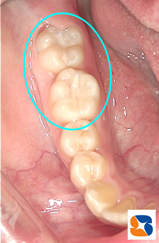

シーラント 白い詰め物 保険

コラム「シーラント 白い詰め物 保険」の画像